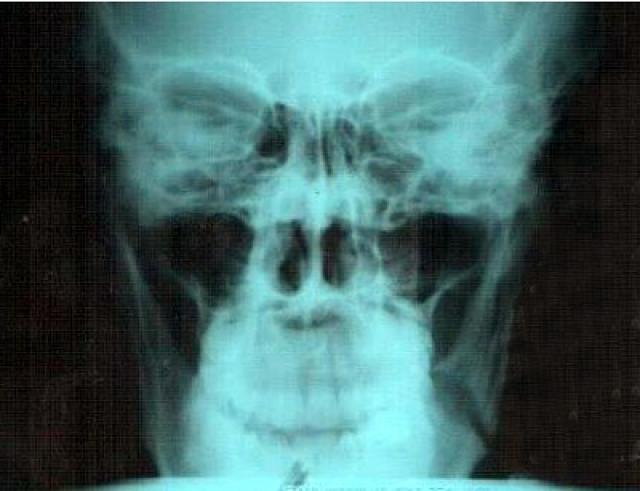

31-го января на литейном заводе произошли неполадки на формовочной линии. Для их исправления был вызван слесарь-ремонтник. Мужчина встал на рольганг для осмотра механизма. В этот момент каретка самопроизвольно двинулась и сильно ударила его по лицу. Медики диагностировали перелом челюсти в четырёх местах.